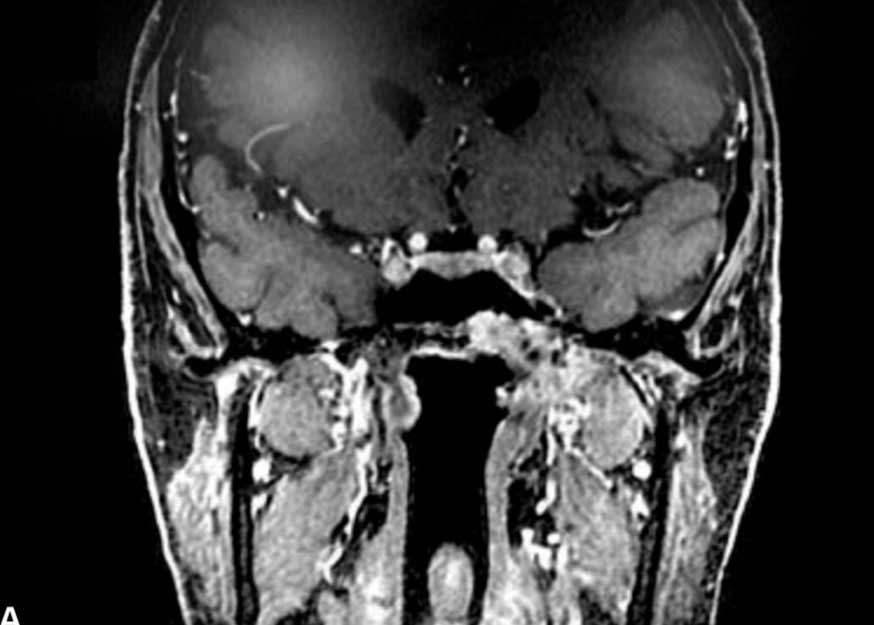

Fossa Pterigopalatina: Anatomia microcirúrgica e sua relevância para a cirurgia da base do crânio

O presente estudo objetiva definir as relações anatômicas da fossa pterigopalatina (FPP) e suas implicações na cirurgia de base de crânio. Descreve-se detalhadamente os limites, intercomunicações e estruturas adjacentes à FPP, anatomia da artéria maxilar e suas variações, com contextualização clínica e cirúrgica. Esse local da base do crânio é a origem de muitos tumores da base do crânio principalmente câncer (carcinoma) e schwanoma.

Fossa Pterigopalatina – Anatomia microcirurgica e sua relevancia para a cirurgia da base do cranio